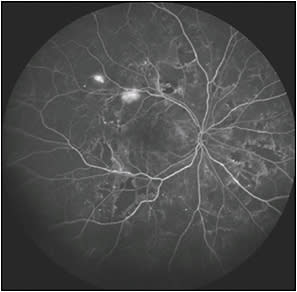

Studies have demonstrated a decrease in the progression of nonproliferative diabetic retinopathy (NPDR) to PDR and even regression from PDR to NPDR with the use of anti-VEGF medications, raising the question of whether these medications should be considered as the first line in the management of DR (Figures 1 and 2).

Figure 1. Ultrawidefield fluorescein angiogram of the right eye with proliferative diabetic retinopathy.